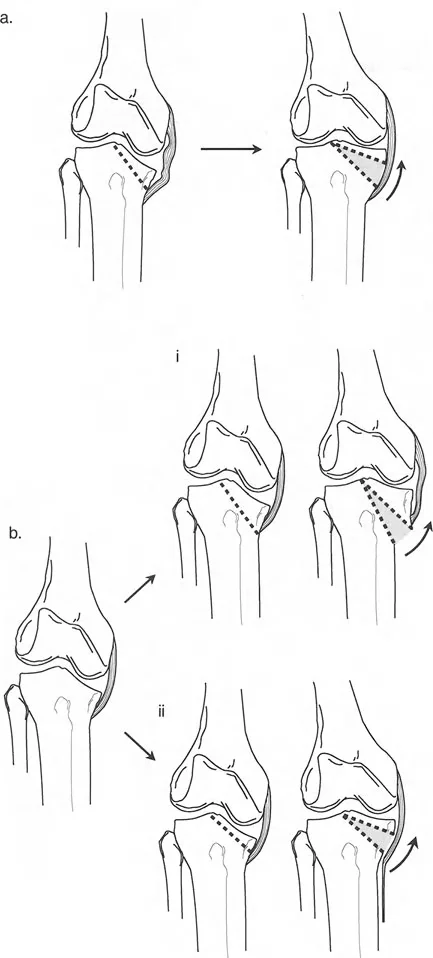

الهضبة الظنبوبية خط "أفضل ملاءمة" مقابل خطين

تحدث هذه الظاهرة من التوجيه غير المتماثل لخط المفصل بشكل أكثر شيوعاً في عظم الساق. عند مواجهة هضبة منخفضة أو سيئة التوجيه، يجب على الجراح اتخاذ قرار استراتيجي حاسم خلال مرحلة التخطيط: هل يجب التعامل مع خط المفصل كخط "أفضل ملاءمة" واحد، أم يجب وصفه بخطين مميزين (واحد للهضبة الإنسية، وواحد للهضبة الوحشية)؟

- نهج خط "أفضل ملاءمة" واحد (تخطيط خارج المفصل):

يجب التعامل مع خط مفصل الركبة كخط "أفضل ملاءمة" واحد لعظم الساق القريب فقط إذا لم تكن هناك نية جراحية لتغيير شكل خط المفصل نفسه. هذا يعني أنك تخطط لقطع عظم خارج المفصل (على سبيل المثال، فتح إسفين في عظم الساق القريب) وتقبل التشوه داخل المفصل. يتم رسم خط "أفضل ملاءمة" عادةً مماساً للهضبة عند نقطتها الأكثر تقعراً، أو عن طريق ربط الهضبة غير المشوهة بالحافة المقابلة. ومع ذلك، في الممارسة العملية، غالباً ما يكون خط "أفضل ملاءمة" المفضل هو ببساطة اعتماد خط لقمة الفخذ، بافتراض أن عظم الفخذ طبيعي (قاعدة بالي للاستبدال). - نهج الخطين (تخطيط داخل المفصل):

إذا كان التصحيح داخل المفصل (مثل رفع الهضبة المباشر) قيد النظر لاستعادة تطابق المفصل، فيجب وصف السطح المفصلي بخطين منفصلين - واحد لكل هضبة. يسمح هذا للجراح بحساب بالضبط عدد الملليمترات من الارتفاع ودرجات الميل الزاوي المطلوبة للجزء المنخفض.

أمثلة كلاسيكية لتشوه خط مفصل الساق

- مرض بلونت (تقوس الساق): في مرض بلونت الشديد لدى الرضع أو المراهقين، تتميز الحالة بانخفاض شديد وميل إنسي للهضبة الظنبوبية الإنسية. إذا رسمت الخطين، فإن خطي الهضبة الإنسية والوحشية يكونان بزاوية حادة بالنسبة لبعضهما البعض، ويتقاطعان بالقرب من مركز الركبة. وهذا يخلق دفعاً تقوسياً شديداً أثناء المشي.

- متلازمة إليس-فان كريفيلد (خلل التنسج الغضروفي الجلدي): تؤدي هذه الحالة الوراثية إلى انخفاض "متدرج" مميز في الهضبة الظنبوبية الوحشية. ومن المثير للاهتمام أن خطي الهضبة غالباً ما يظلان متوازيين لبعضهما البعض، لكنهما يقعان على مستويات أفقية مختلفة تماماً، مما يخلق فرقاً كبيراً في المستوى وتشوهًا شديدًا في وضعية الركبة (valgus).

سوء توجيه لقمة الفخذ السطح المستدير المتسامح

بينما الهضبتان الظنبوبيتان مسطحتان نسبياً (مما يجعلهما شديدتي الحساسية للدرجات والتغيرات الزاوية)، فإن لقم الفخذ مستديرة تشريحياً. هذا الاختلاف الهندسي الأساسي يغير تماماً كيفية تعاملنا مع تشوهات خط مفصل الفخذ مقارنةً بتشوهات عظم الساق.

في عظم الفخذ، قد تكون اللقم الإنسية أو الوحشية على مستويات أو اتجاهات مختلفة بسبب عدة أمراض خطيرة:

* توقف النمو الإنتاني: عدوى في مرحلة الطفولة (التهاب العظم والنقي / التهاب المفاصل الإنتاني) تدمر صفيحة النمو لقمة الفخذ الوحشية مما يؤدي إلى لقمة وحشية ناقصة التنسج، سيئة التوجيه، و "متدرجة" مقارنة بالجانب الإنسي السليم الذي ينمو.

* التئام العظم بعد الصدمة بشكل خاطئ: كسر سالتر-هاريس لدى الأطفال أو كسر بين اللقمتين لدى البالغين يلتئم بشكل سيء ينتج عنه درجة مميزة و/أو سوء توجيه للقم.

* توقف النمو المركزي (تشوه ذيل السمكة): توقف النمو في المركز الدقيق لصفيحة النمو الفخذية البعيدة يتسبب في سوء توجيه اللقمتين وانحدارهما نحو المنتصف، مما يخلق مظهراً كلاسيكياً "لذيل السمكة" على صور الأشعة السينية الأمامية الخلفية.

لماذا عظم الفخذ أكثر تسامحاً

تؤدي الهضبتان الظنبوبيتان بمستويات أو اتجاهات مختلفة إلى عدم تطابق فوري وشديد في المفصل، وتحميل نقطي، وقص غضروفي، وعدم استقرار سريري. هذه هندسة أساسية: السطح المسطح لا يمكن أن يستوعب درجة.

على العكس من ذلك، يمكن للسطح المفصلي الظنبوبي المطابق أن يستوعب سطح الفخذ المستدير المزاح أو سيء التوجيه بشكل أفضل بكثير. نظراً لأن لقم الفخذ كروية، يمكنها غالباً الاستمرار في التدحرج والانزلاق على عظم الساق المسطح نسبياً حتى لو تغيرت ارتفاعاتها أو زواياها النسبية قليلاً.

على سبيل المثال، يبدو سوء توجيه "ذيل السمكة" الدرامي الناتج عن توقف النمو المركزي مخيفاً على الأشعة السينية، ولكنه غالباً لا يتعارض بشكل كبير مع وظيفة المفصل أو استقرار الأربطة أو نطاق الحركة. قد يعاني المريض من انحراف في المحور الميكانيكي، لكن المفصل نفسه يستمر في الحركة بسلاسة.

التأثير الجراحي: بسبب هذا التسامح الهندسي، يمكن غالباً إعادة محاذاة سوء المحاذاة الناتج عن إزاحة لقمة الفخذ الأحادية أو سوء توجيهها باستخدام قطع عظم الفخذ فوق اللقمي خارج المفصل. لا تحتاج دائماً إلى تقسيم اللقم وإجراء عملية داخل المفصل عالية المخاطر. على النقيض من ذلك، فإن عدم الاستقرار الشديد الناتج عن درجات عظم الساق يتطلب دائماً تقريباً قطع عظم حقيقي داخل المفصل (رفع الهضبة) بدلاً من مجرد تصحيح في الميتافيزيس، لمنع التدمير السريع للمفصل.